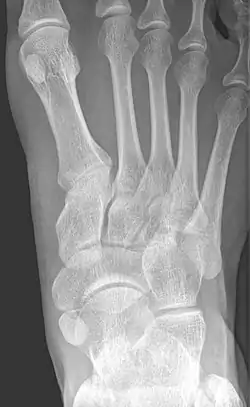

From left to right: Type 1, 2 and 3

Type 2 on one foot (dark arrow) and type 3 on the other (white arrow)